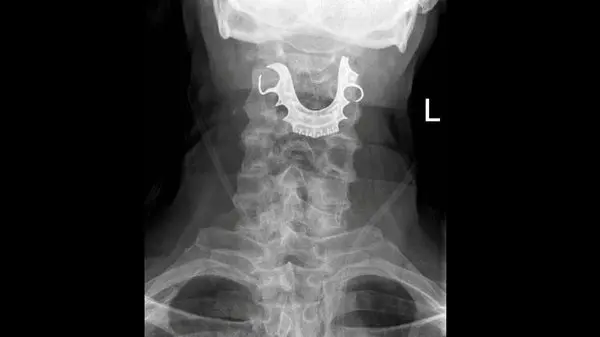

به گزارش گروه ترجمه رکنا، پزشکان بیمارستان بریتانیا با مراجعه مردی 72 ساله به بیمارستان با شکایت از گلو درد و تنگی نفس با معاینات پزشکی با صحنه ای عجیب در گلوی پیرمرد مواجه شدند.

از قرار معلوم هنگام جراحی دندان مصنوعی بیمار داخل دهانش بود که بی توجهی پزشکان و پرستاران موجب شد تا دندان داخل گلویش گیر کند و راه تنفسی او را ببندد.

بیمار 72 ساله مدعی بود که پس از به هوش آمدن در بیمارستان پزشکان به او گفتند که دندانش گم شده و او تا زمان مرخص شدن بدون دندان مانده بود تا این که چندی پیش متوجه گلو درد و خونریزی شدید و بسته شدن راه تنفسی اش شد که با مراجعه به بیمارستان راز بی احتیاطی پزشکان فاش شد.